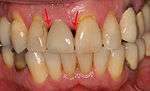

From these theoretical risks, derive the real world complications. Long-term failures are due to either loss of bone around the tooth and/or gingiva due to peri-implantitis or a mechanical failure of the implant. Because there is no dental enamel on an implant, it does not fail due to cavities like natural teeth. While large-scale, long-term studies are scarce, several systematic reviews estimate the long-term (five to ten years) survival of dental implants at 93–98 percent depending on their clinical use.[1][2][3] During initial development of implant retained teeth, all crowns were attached to the teeth with screws, but more recent advancements have allowed placement of crowns on the abutments with dental cement (akin to placing a crown on a tooth). This has created the potential for cement, that escapes from under the crown during cementation to get caught in the gingiva and create a peri-implantitis (see picture below). While the complication can occur, there does not appear to be any additional peri-implantitis in cement-retained crowns compared to screw-retained crowns overall.[40] In compound implants (two stage implants), between the actual implant and the superstructure (abutment) are gaps and cavities into which bacteria can penetrate from the oral cavity. Later these bacteria will return into the adjacent tissue and can cause periimplantitis. As prophylaxis these implant interior spaces should be sealed.[41]